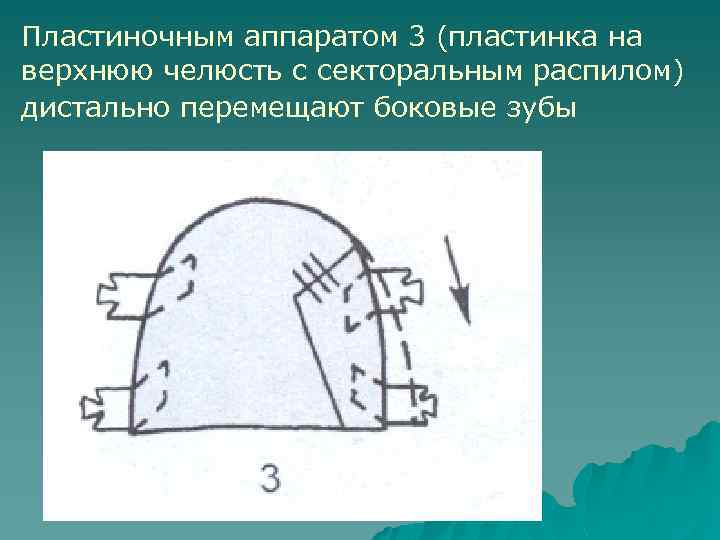

Пластиночным аппаратом 3 (пластинка на верхнюю челюсть с секторальным распилом) дистально перемещают боковые зубы